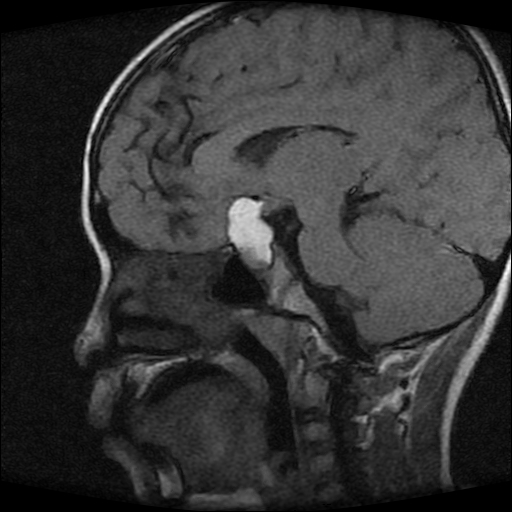

男性,12岁。反复头痛呕吐半月。脑积液无异常。病变部位ct值32hu,dwi无异常。

鞍上为主,累及鞍内,垂体受压位于鞍底。mri呈短t1、长t2信号,不太支持生殖细胞肿瘤,首考颅咽管瘤。

鞍内囊性占位性病变,t1wi、t2wi,均为高信号影。ct平扫为等密度。发病年龄较小。故首先考虑颅咽管瘤,可以做ct增强扫描